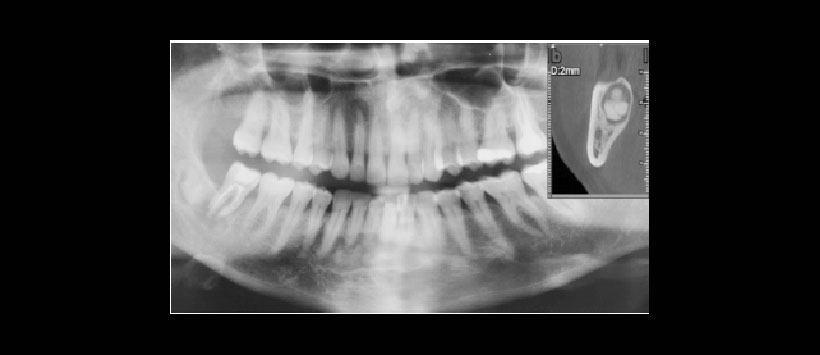

Figura 1: Radiografìa panorámica que muestra múltiples imágenes radiopacas a nivel periapical de la región anteroinferior y molar posteriore. Corte transaxial a nivel distal de la pieza 47. Muestra una imagen heterogenea, signos radiográficos sugerentes de displasia cemento-ósea florida. Imágenes correspondientes a una paciente femenino de 49 años de edad cuyo motivo de consulta es el dolor mandibular en la region mandibular derecha.

Figura 3: Radiografía de control. Postoperatorio 2 años.